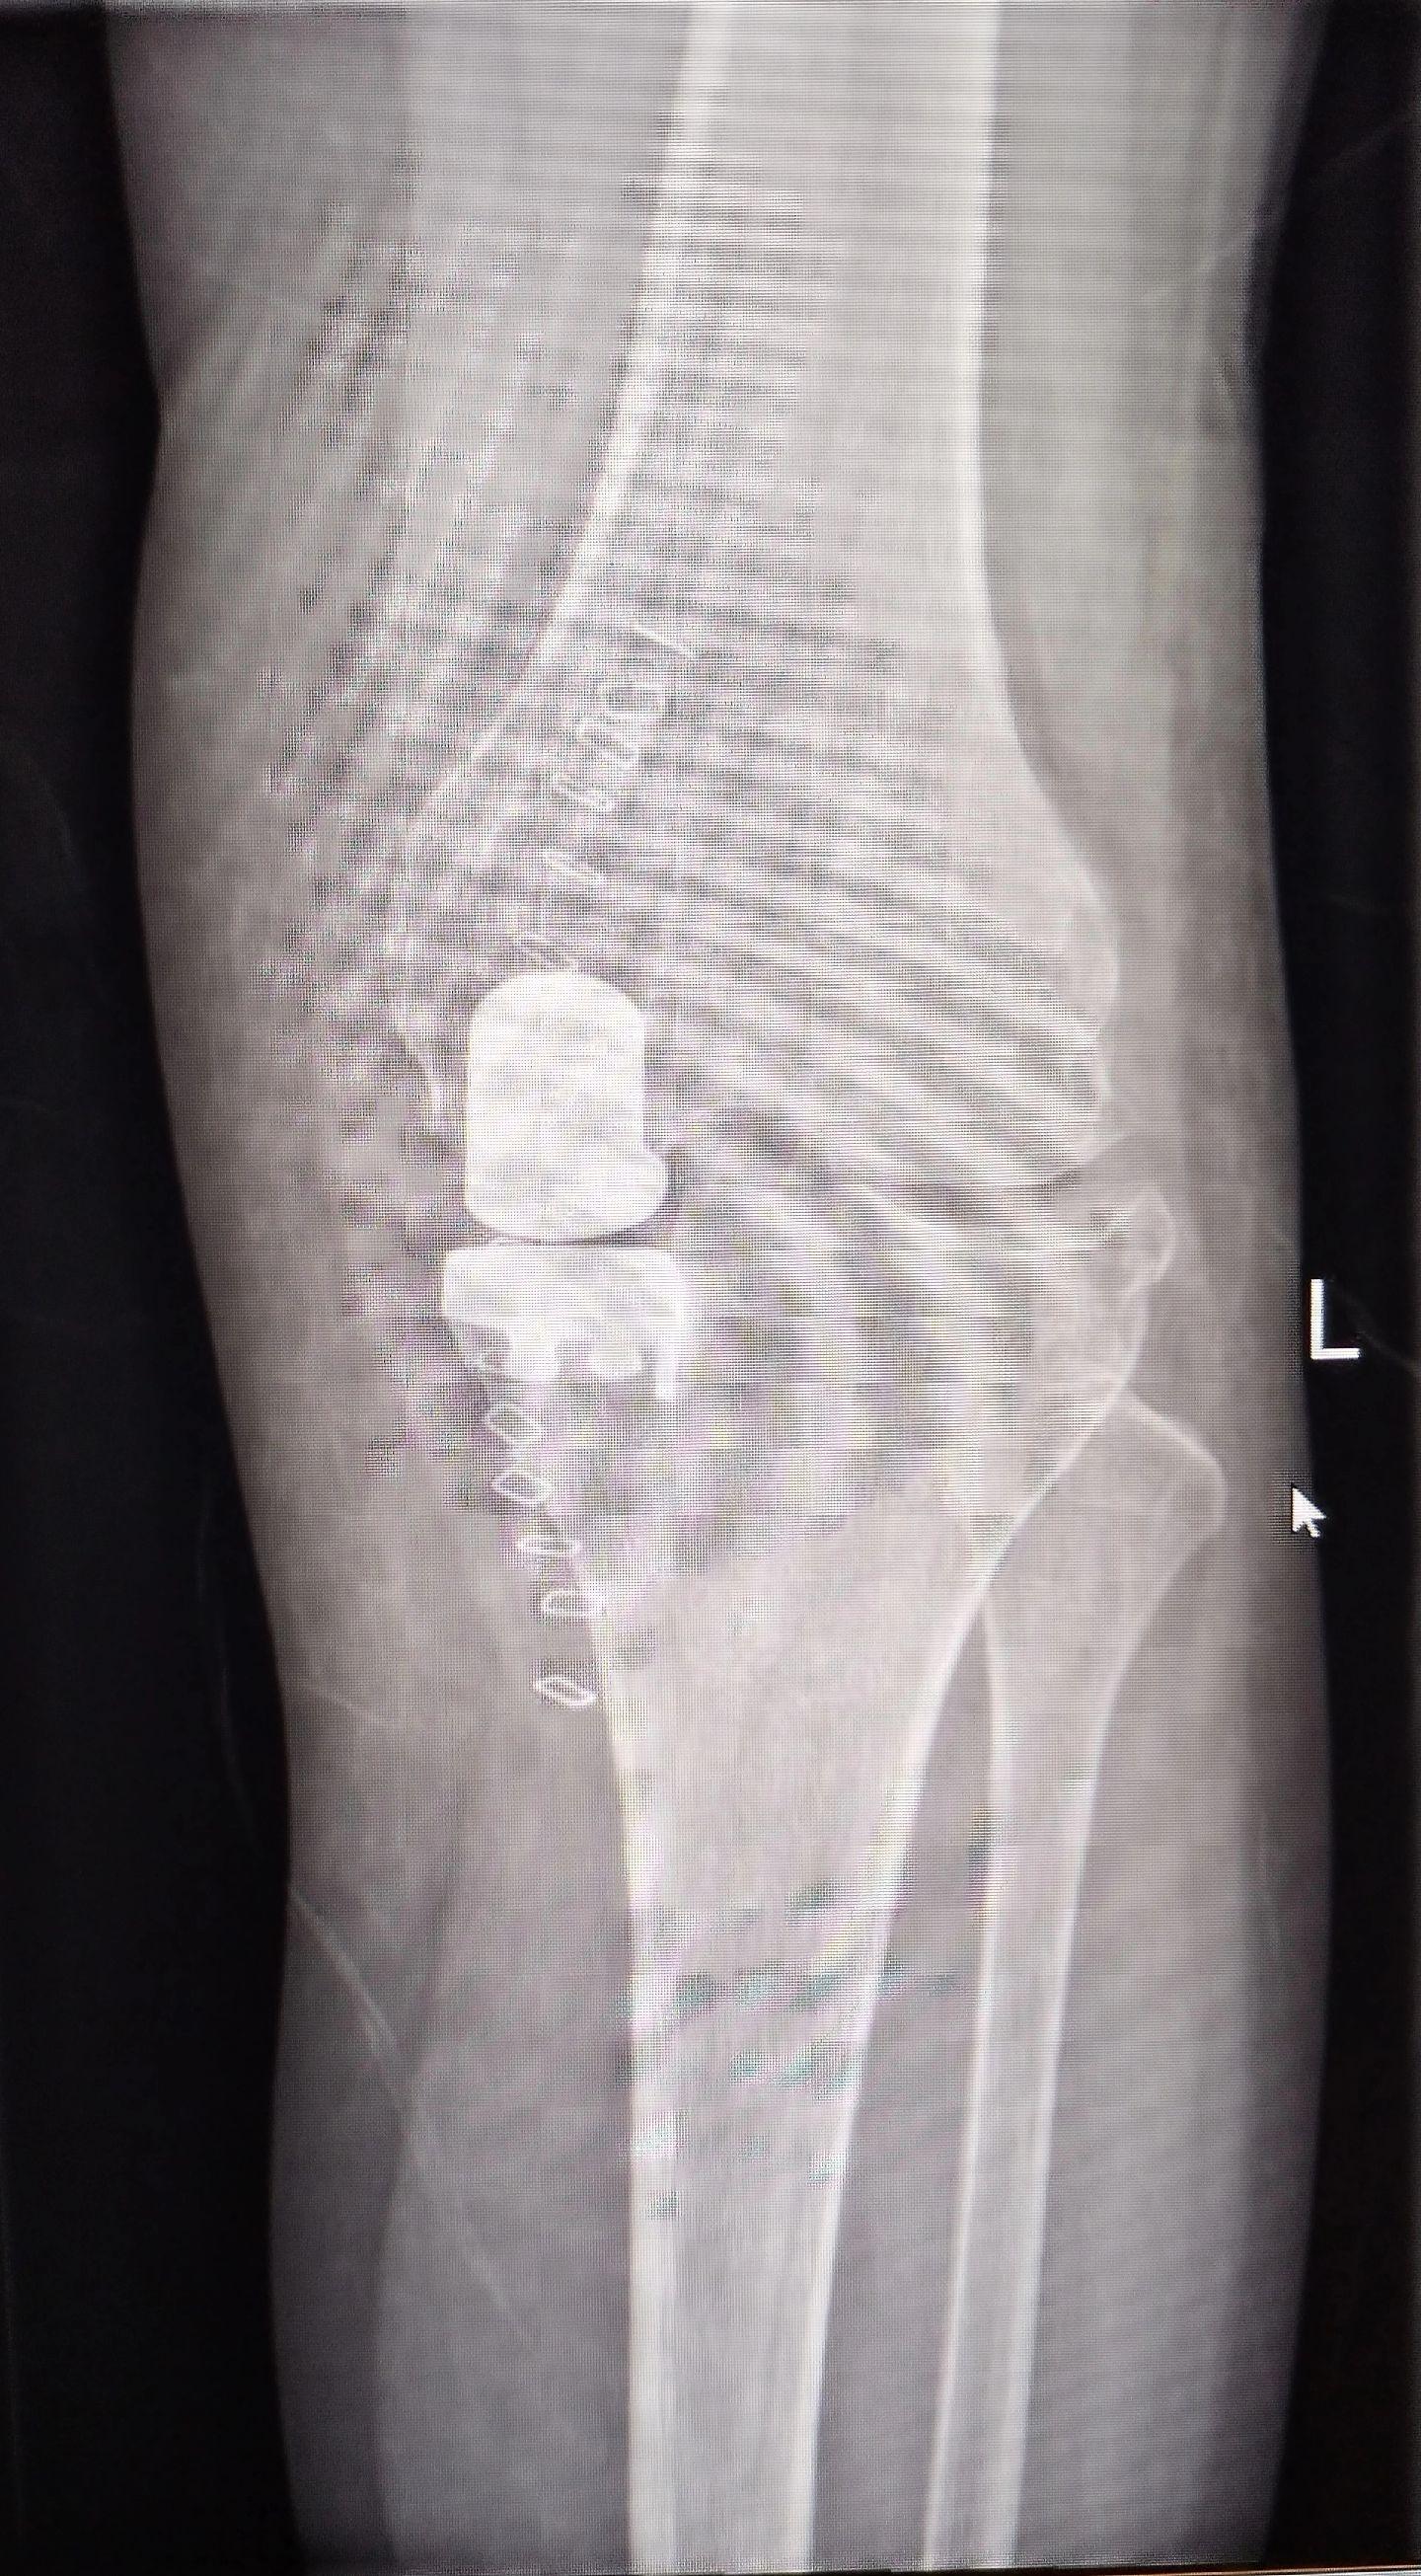

UKA单髁置换。膝关节骨关节炎,同期双侧单髁置换,术后四天出院,快速康复,省医关节外科🌹